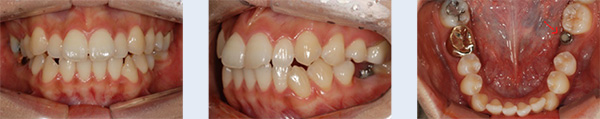

아랫니가 앞니보다 바깥쪽으로 위치한 증상을 바로잡고 빠진 윗니를 수복하기 위해 내원한 37세 남성입니다. 검사 결과 위쪽 영구치 3개 결손 된 상태였으며, 아래턱이 전방 위치된 주걱턱(골격성 3급 부정교합)으로 진단 하였으나 양악수술 없이 치료를 원하셔서 치아교정과 임플란트 치료를 병행하였습니다.

① 결손된 위 앞니, 송곳니 공간 재형성

② 교정용 미니스크류를 이용하여 아래 전체 치열 후방 이동

약 2년 간의 교정 치료 후 정상적인 앞니 배열과 임플란트 식립에 필요한 공간이 확보되어 보철 치료를 한 후 교정 장치를 제거하였습니다. 거꾸로 물려 정상적인 기능이 어려웠던 앞니의 심미적, 기능적 회복이 동시에 이루어졌습니다.